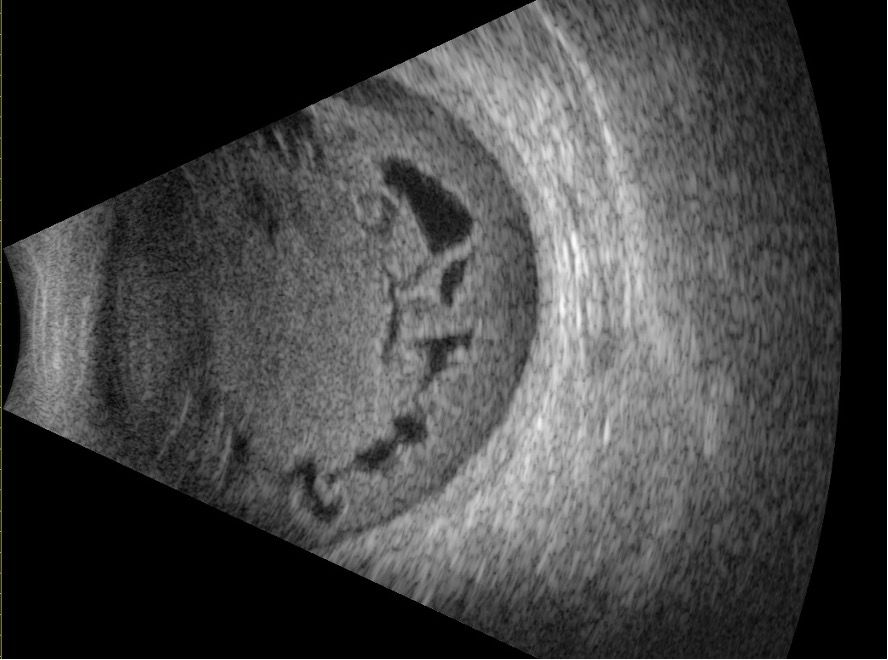

Tumeurs intraoculaires

L'échographie est essentielle pour le diagnostic et la caractérisation des tumeurs. Le mélanome choroïdien se présente typiquement comme une lésion en dôme ou en champignon, avec une excavation choroïdienne et une réflectivité interne basse. Le rétinoblastome montre des calcifications hyperéchogènes avec cône d'ombre. Les métastases choroïdiennes sont souvent plates, multifocales, avec une réflectivité interne moyenne-haute irrégulière. L'hémangiome choroïdien présente une réflectivité haute et régulière.

Tumeurs du segment antérieur

Les tumeurs de l'iris et du corps ciliaire (mélanome, kyste, métastase) sont caractérisées par l'UBM : extension en profondeur, envahissement de l'angle, rapport avec le cristallin et le corps ciliaire. L'UBM permet de mesurer l'épaisseur tumorale avec précision, critère pronostique important dans le mélanome irien. Elle détecte également l'extension antérieure de tumeurs choroïdiennes.